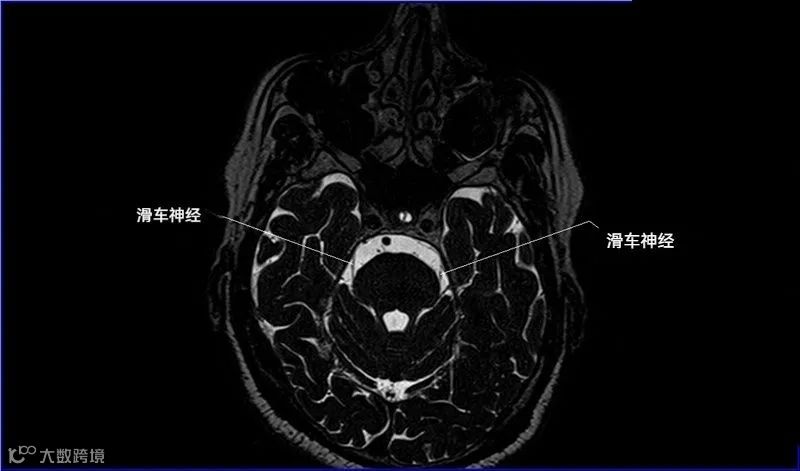

一嗅二视三动眼,四滑五叉六外展,

七面八听九舌咽,迷走及副舌下全。